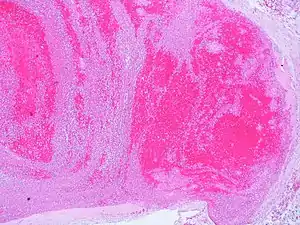

Low magnification micrograph showing laminations in a thrombus in a fatal pulmonary embolism. H&E stain.

| A recent pulmonary thrombo-embolus with prominent lines of Zahn. The pale areas consist of fibrin and platelets. The red areas consist of erythrocytes. | |

Lines of Zahn are a characteristic of thrombi.[1] They have visible and microscopic alternating layers (laminations).[2][3] Platelets mixed with fibrin form lighter layers.[2] Red blood cells form darker layers.[2] Sometimes, the term "lines of Zahn" only refers to the lighter layers.[4]